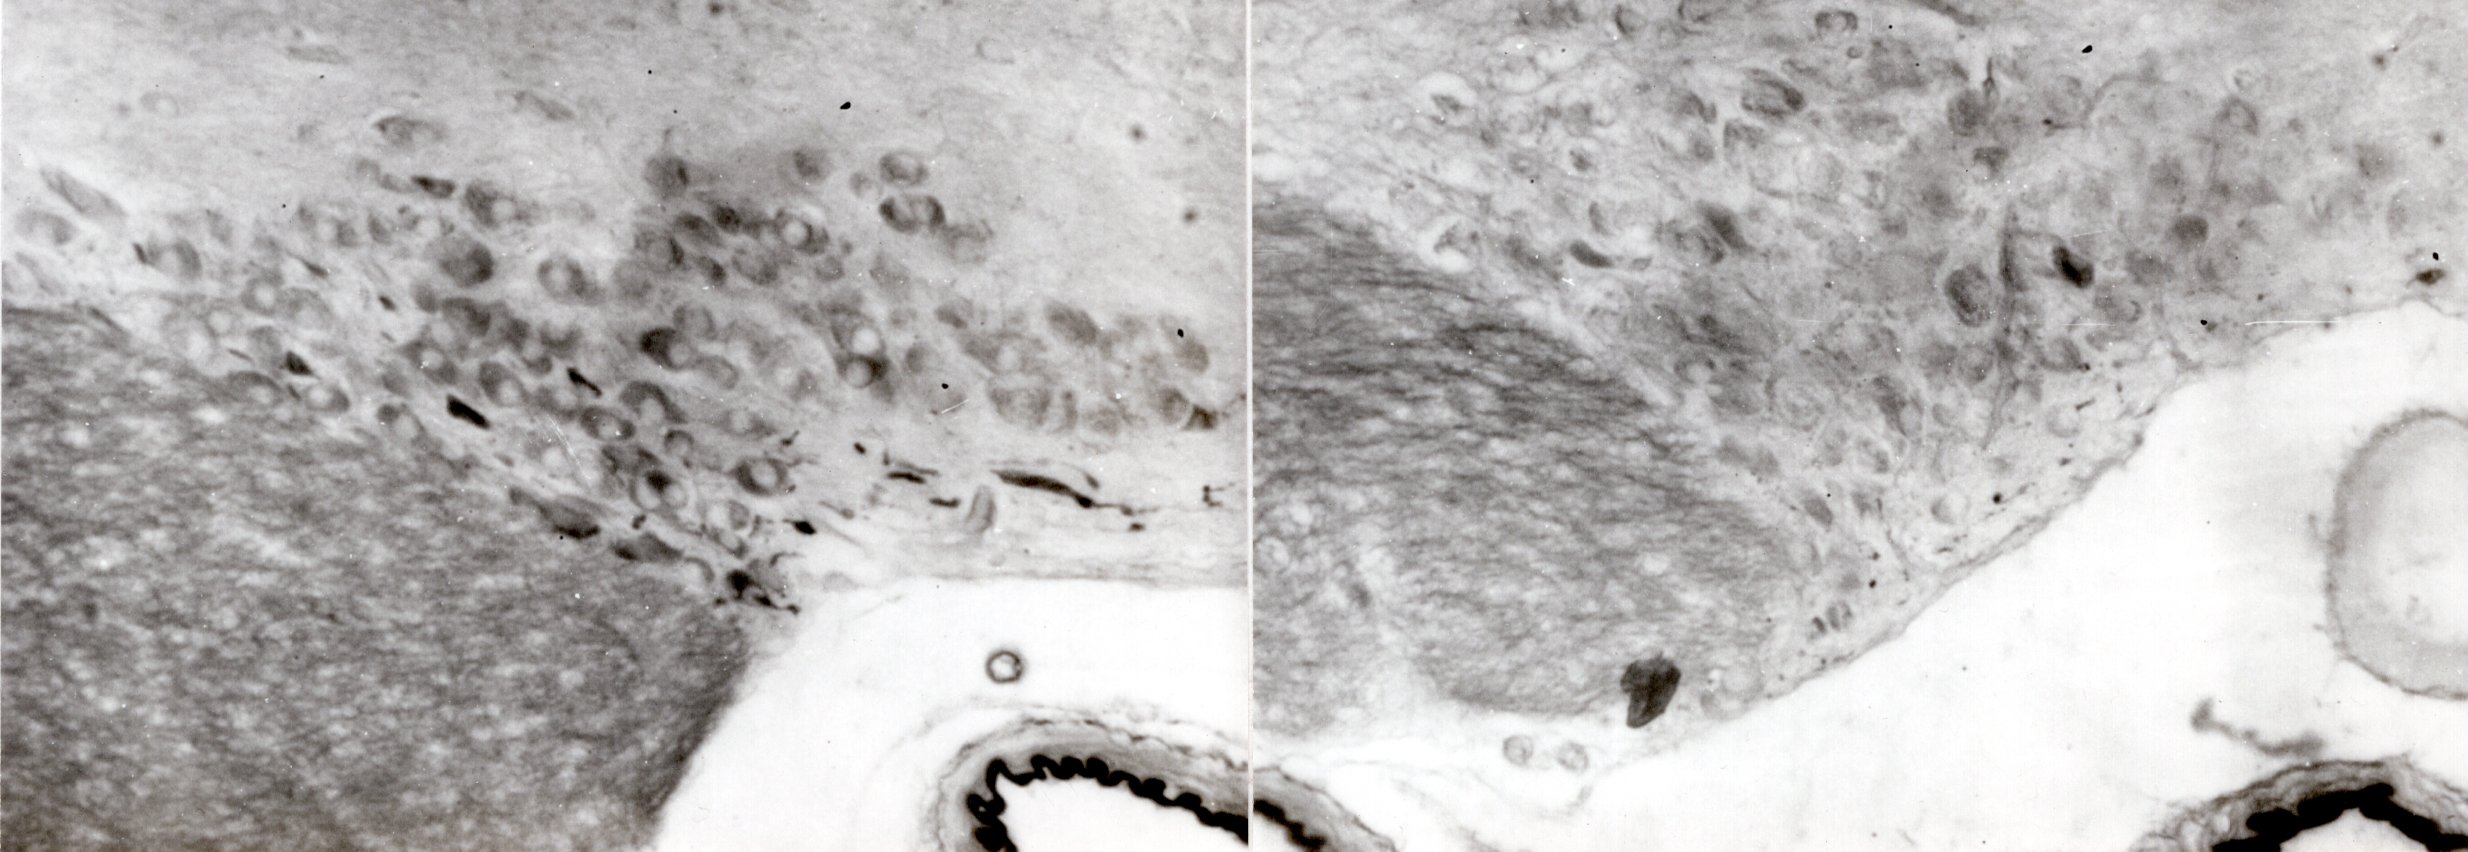

ウズラで培った技術を用いて、ラットの視索上核へ両側性にチューブに詰めたピューロマイシンを埋め込み、メタボリックケージで尿量と飲水量を測定しました。ラットの数はわずか3頭でしたが(別に対照群として3頭)、植え込んだチューブの位置を切片で確認しており、そのうちの1頭は視索上核を覆うように埋め込まれていて(下のグラフのa)、組織を作成してアルデヒドフクシン(AF)染色をするとにニューロン内の染色される物質がほとんどなくなっていて(下の組織の写真の右側、左は対照)、飲水量と尿量の増加とよく対応していました。